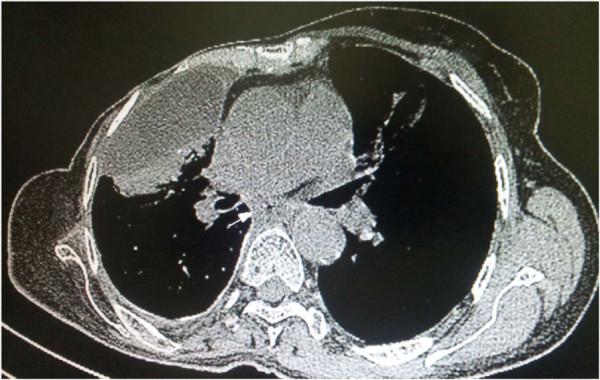

A 56 year-old non smoking woman, with no alcohol intake and no familial history of cancer; followed in the National Institute of Oncology of Rabat Morocco since 1999 for breast carcinoma, presented on consultation on January 2011 with dysphagia. Breast cancer was treated with modified radical mastectomy, 6 courses of chemotherapy based on CMF regimen and radiotherapy to breast, inner mammary chain and to pelvis as castration. Less than a year later, a renal right mass was discovered incidentally. Enlarged nephrectomy realized and showed renal cell carcinoma. A local and metastatic breast cancer recurrence occurred in 2007. Patient had 2 lines of chemotherapy and 2 lines of hormonotherapy with Letrozole and Tamoxifen assuring a stable disease. On January 2011, the patient presented dysphagia. Oesogastric endoscopy showed middle esophagus stenosing mass. Biopsy revealed adenocarcinoma. No evidence of metastasis was noticed on computed tomography and breast disease was controlled. Palliative brachytherapy to esophagus was delivered. Patient presented dysphagia due to progressive disease 4 months later. Jejunostomy was proposed but the patient refused any treatment. She died on July 2011.

一名56岁不吸烟女性,无饮酒史且无癌症家族史;自1999年起在摩洛哥拉巴特国家肿瘤研究所因乳腺癌接受随访,2011年1月因吞咽困难前来就诊。乳腺癌采用改良根治性乳房切除术、基于CMF方案的6个疗程化疗以及对乳房、内乳链和盆腔进行放疗作为去势治疗。不到一年后,偶然发现右肾肿物。实施扩大肾切除术,结果显示为肾细胞癌。2007年发生局部和转移性乳腺癌复发。患者接受了2线化疗和2线激素治疗,使用来曲唑和他莫昔芬,病情稳定。2011年1月,患者出现吞咽困难。食管胃内镜检查显示食管中段有狭窄肿物。活检显示为腺癌。计算机断层扫描未发现转移迹象,乳腺疾病得到控制。对食管进行了姑息性近距离放疗。4个月后,患者因病情进展出现吞咽困难。建议行空肠造口术,但患者拒绝任何治疗。她于2011年7月去世。